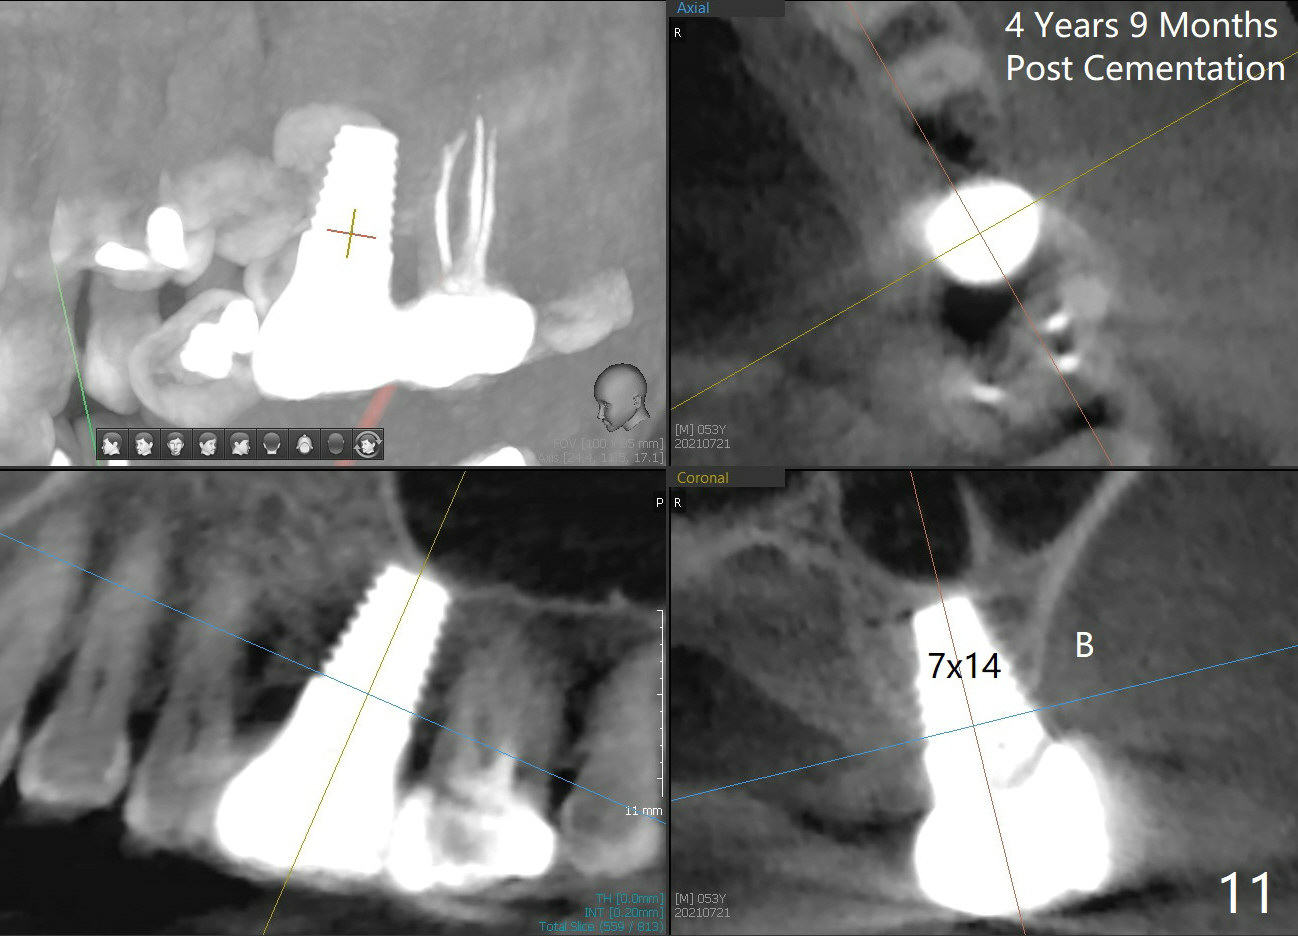

Twenty-one months postop, the patient returns for #15 RCT. PAs show that although there is a narrow space in the original mesial socket (Fig.9 *), the 1st thread space is partially obliterated with the bone (<). In contrast, the distal 1st thread space is completely obliterated (Fig.10 >). After the RCT, impression is taken for #14 and 15. Although there is no sign of periimplantitis, the 7x14 mm implant looks too large for the site with possible buccal thread exposure 4 years 9 months post cementation (Fig.11). To reduce complications, a much small fixture will be at #30.